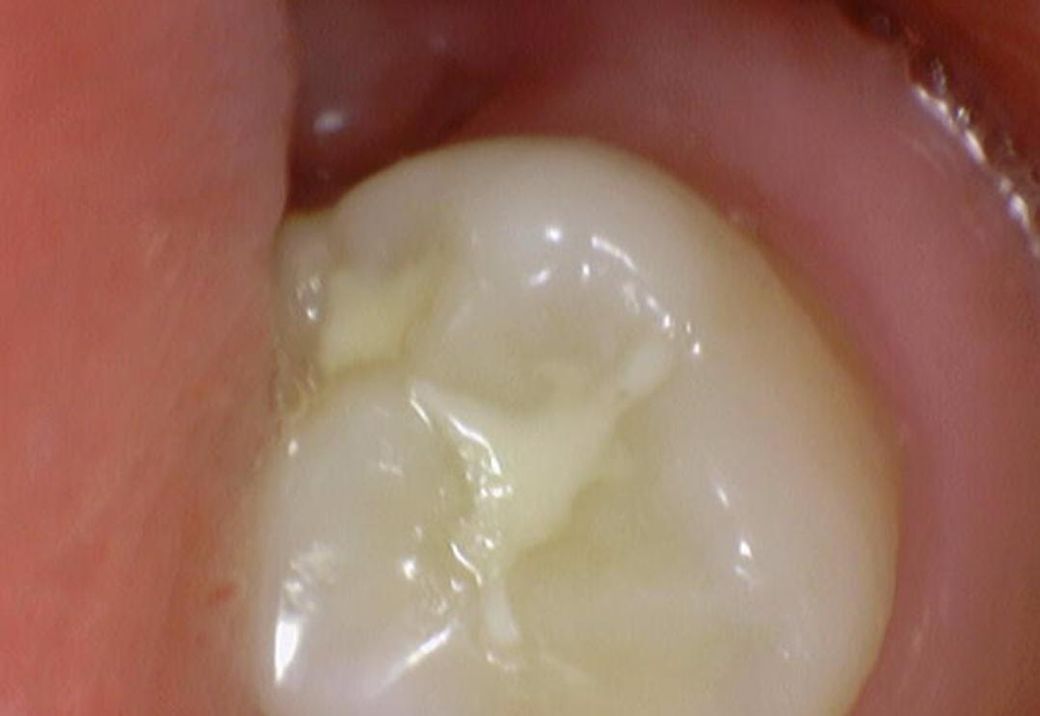

여쭙고 싶은건 깨진건(이 일부가 떨어져나감) 저도 보이기는 하는데

이게 시간이 지날수록 발치가 이어질 안좋은 크랙인지, 아니면 일단 10년 정도는 조심스럽게 그냥 살아도 괜찮은, 흔한 경우인지 입니다

밑에 구강내부 사진(16,17,26,27번 치아)들에서

치료가 반드시 필요한 치아는 몇번째 사진 이런식으로 설명 부탁드립니다

파절된 부위가 보이긴 합니다 하지만 금이 깊게 진행될 정도로 보이는 것은 아닌 것으로 판단이 됩니다 정확한 확인은 직접 확인을 해 봐야 알 수 있습니다.

예전에 치아 사이에 레진치료를 한곳이 떨어진 부분이 몇군데 잇는거 같습니다. 작은 사진을 찍어보시고 치료를 받으시는게 좋을것같습니다.